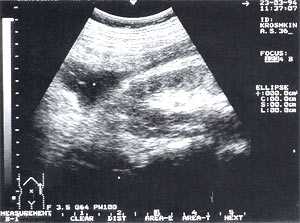

Оментобурсит (рис. 3) встречается в 28,4% случаев (из них 48% у мужчин и 52% у женщин). Некоторые авторы обозначают эту патологию как "псевдокиста поджелудочной железы". Отмечен объем таких образований от 5мл (малые объемы необходимо дифференцировать с сосудистыми аневризмами) до 3 л и более. Скорость формирования оментобурсита при остром панкреатите от 2 - 4 дн. от начала заболевания до 2 - 4 нед. При ультразвуковом исследовании оментобурсит представлен в виде анэхогенного образования с четкими контурами, неправильной или округлой формы, чаще с однородной структурой, с толщиной стенок 0,2 - 0,4 см. При эхографическом мониторинге утолщение стенки до 0,5 - 1,0 см с появлением неоднородности структуры следует расценивать как сонографический признак абсцедирования.

Рис. 3. Псевдокиста поджелудочной железы при остром панкреатите в виде анэхогенного образования с четкими контурами, однородной структурой, с наличием гиперэхогенных включений (детрит поджелудочной железы).